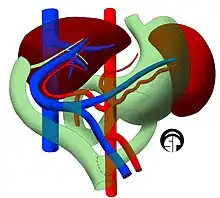

Technique

Before transplantation, liver-support therapy might be indicated (bridging-to-transplantation). Artificial liver support like liver dialysis or bioartificial liver support concepts are currently under preclinical and clinical evaluation. Virtually all liver transplants are done in an orthotopic fashion; that is, the native liver is removed and the new liver is placed in the same anatomic location.[7] The transplant operation can be conceptualized as consisting of the hepatectomy (liver removal) phase, the anhepatic (no liver) phase, and the postimplantation phase. The operation is done through a large incision in the upper abdomen. The hepatectomy involves division of all ligamentous attachments to the liver, as well as the common bile duct, hepatic artery, hepatic vein and portal vein. Usually, the retrohepatic portion of the inferior vena cava is removed along with the liver, although an alternative technique preserves the recipient's vena cava ("piggyback" technique).

The donor's blood in the liver will be replaced by an ice-cold organ storage solution, such as UW (Viaspan) or HTK, until the allograft liver is implanted. Implantation involves anastomoses (connections) of the inferior vena cava, portal vein, and hepatic artery. After blood flow is restored to the new liver, the biliary (bile duct) anastomosis is constructed, either to the recipient's own bile duct or to the small intestine. The surgery usually takes between five and six hours, but may be longer or shorter due to the difficulty of the operation and the experience of the surgeon.

Living donor liver transplantation (LDLT) has emerged in recent decades as a critical surgical option for patients with end stage liver disease, such as cirrhosis and/or hepatocellular carcinoma often attributable to one or more of the following: long-term alcohol use disorder, long-term untreated hepatitis C infection, long-term untreated hepatitis B infection. The concept of LDLT is based on (1) the remarkable regenerative capacities of the human liver and (2) the widespread shortage of cadaveric livers for patients awaiting transplant. In LDLT, a piece of healthy liver is surgically removed from a living person and transplanted into a recipient, immediately after the recipient's diseased liver has been entirely removed.

In a typical adult recipient LDLT, 55 to 70% of the liver (the right lobe) is removed from a healthy living donor. The donor's liver will regenerate approaching 100% function within 4–6 weeks, and will almost reach full volumetric size with recapitulation of the normal structure soon thereafter. It may be possible to remove up to 70% of the liver from a healthy living donor without harm in most cases. The transplanted portion will reach full function and the appropriate size in the recipient as well, although it will take longer than for the donor.[14]